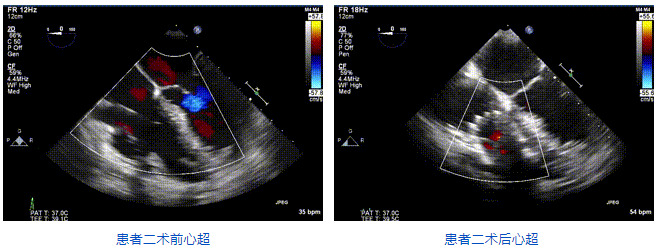

2021年12月24日,復(fù)旦大學(xué)附屬中山醫(yī)院葛均波院士團隊成功應(yīng)用LuX-Valve Plus為一例極重度三尖瓣反流(TR)合并房顫、房缺的患者完成了經(jīng)血管三尖瓣置換術(shù),這是在前基礎(chǔ)上,本周完成的第三例經(jīng)血管三尖瓣置換手術(shù),葛均波院士、周達新教授等與心外科魏來教授、賴顥教授,心超室的潘翠珍教授、李偉教授及麻醉科的郭克芳教授共同完成了本周手術(shù),均獲得圓滿成功!患者術(shù)后超聲顯示無TR,臨床癥狀明顯改善。本周手術(shù)的成功也為LuX-Valve Plus救治性臨床研究添上了濃墨重彩的一筆。

本周三例接受LuX-Valve Plus經(jīng)血管三尖瓣置換術(shù)的患者中,第一例患者為冠狀動脈旁路移植術(shù)+Bentall+二尖瓣成形術(shù)后;第二例患者為永久起搏器植入術(shù)后,存在跨三尖瓣導(dǎo)線;第三例患者合并房顫、房缺及左心耳封堵術(shù)后。

三例患者入院后,葛均波院士團隊周達新教授、潘文志教授、張源博士、陳莎莎博士及心超室的潘翠珍教授、李偉教授對患者的情況進行詳細評估和討論,最終決定為三例患者選擇LuX-Valve Plus40mm、50mm和50mm型號的瓣膜進行手術(shù)治療。手術(shù)后即刻拔除氣管插管,術(shù)后患者三尖瓣反流癥狀得到顯著改善,復(fù)查心超結(jié)果顯示人工三尖瓣瓣膜支架固定穩(wěn)定,瓣葉關(guān)閉形態(tài)未見異常,未見明顯反流。